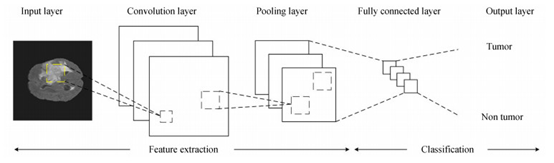

多模态融合: